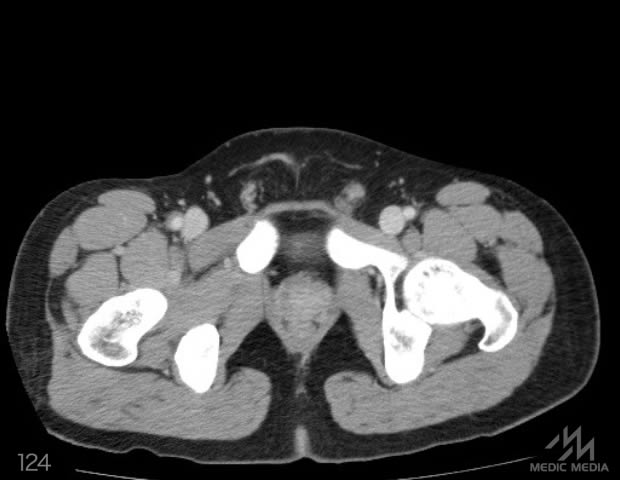

造影CT

スライド(画像下)を動かしながら,CTで臓器の位置を確認してみましょう.

消化器